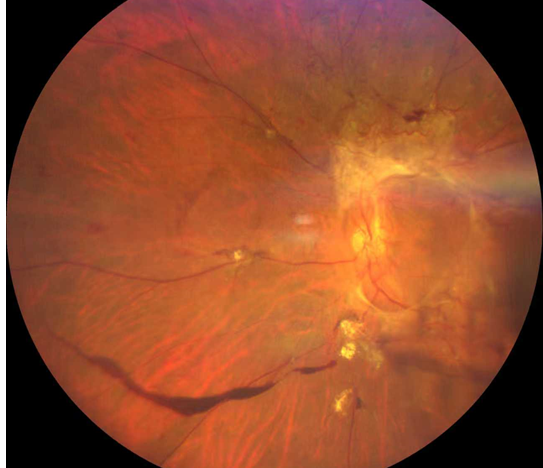

廈門眼科中心的檢查結(jié)果讓全家倒吸一口涼氣:

右眼視力0.05,左眼僅余眼前光感;

雙眼被確診為Ⅱ期增殖性糖尿病視網(wǎng)膜病變(以下簡(jiǎn)稱“糖網(wǎng)”),并伴有黃斑水腫。

糖尿病視網(wǎng)膜病變

這意味著,如果再晚來幾天,視網(wǎng)膜損傷將不可逆轉(zhuǎn),他將永遠(yuǎn)失去光明。

萬幸,眼底病科王曉波主任為鄭先生實(shí)施了左眼25G微創(chuàng)萬速玻璃體切割手術(shù)聯(lián)合抗VEGF藥物注射治療,手術(shù)很順利。術(shù)后鄭先生左眼視力逐漸恢復(fù)到0.5。